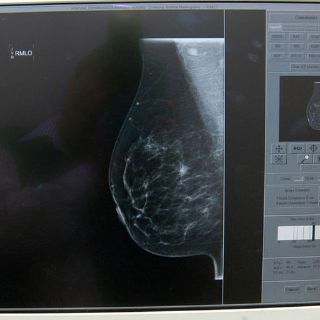

Además, aunque en Jalisco el año pasado se realizaron cerca de 52 mil mastografías y éste se planea cerca de 80 mil –de las cuales ya van cerca de 51 mil–, este estudio se recomienda para mujeres mayores de 40 años.

Para las menores de esa edad, este estudio no es tan efectivo, por lo que, en caso de sospecha, pueden platicar con su médico sobre la factibilidad de hacer un ecosonograma o incluso, una resonancia magnética, explica Daneri Navarro.

También hay que aumentar el entrenamiento de los radiólogos para que puedan discriminar bien entre lo que sí es sospechoso o que apunta a que es cáncer de mama, y lo mismo puede decirse de los médico de primer y segundo nivel.